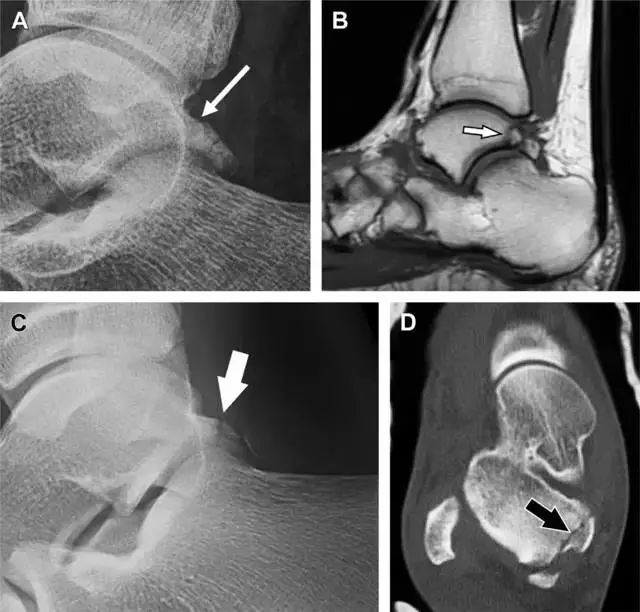

距骨外侧突骨折

距骨外侧突骨折常因踝外翻背屈时,跟骨上外侧面撞击距骨外侧突下缘导致,或偶尔由踝内翻引起,被称为「滑雪板者骨折」。这种骨折只能在踝关节正位片上发现,而且外踝远端表面软组织肿胀往往是一个重要线索(图 4)。

图 4 距骨外侧突骨折。A 正位片示内翻损伤所致的距骨外侧突撕脱性骨折(箭头);B 另一位患者,踝外翻损伤导致典型的「滑雪板者骨折」,X 片上可见一较大的三角形骨折块(方框);C 第二位患者的 MRI 矢状位 T1 加权像示横行骨折(箭头)。

距骨后突骨折

距骨后突有内侧结节和外侧结节,距骨后突内侧结节撕脱性骨折常发生在背屈内旋的*力暴**作用下。严重跖屈时,胫骨后缘和跟骨挤压距骨后突外侧结节呈楔形,易发生粉碎性骨折。这些骨折细微且需与三角骨鉴别。侧位片观察距骨后突骨折最佳,常规拍片很难发现,当高度怀疑这种骨折又没法做 CT 时,建议加做多个角度的外旋斜位片(图 5)。

图 5 距骨后突骨折。侧位片(A)和 MRI 矢状位 T1 加权像(B)均示后外侧突的简单骨折(箭头),再次阅片时才发现 X 线片上的骨折;侧位片(C)和 CT 横断面图像示后内侧突的粉碎型骨折(箭头)。

跟骨前突骨折

呈 Y 形的分歧韧带附着于跟骨前突上,是维持踝关节跖屈和背屈稳定性的重要结构。跟骨前突骨折常发生于足跖屈内旋、分歧韧带被牵拉时,或者足背屈外旋、骰骨和距骨挤压前突时。而这些骨折在初次 X 线检查时常常被漏诊掉。踝部侧位片诊断这些骨折最佳,准确诊断的关键点在于,必须仔细查看是否存在骨皮质中断(图 6)。如果侧位片可疑,建议加做斜位片协助诊断。

图 6 跟骨前突骨折。A 侧位片示跟骨前突骨折(箭头),与舟骨的重叠使骨折显示模糊;B 另一位患者的侧位片示内翻损伤所致的骨折(箭头),这种损伤机制引起小块的骨折。